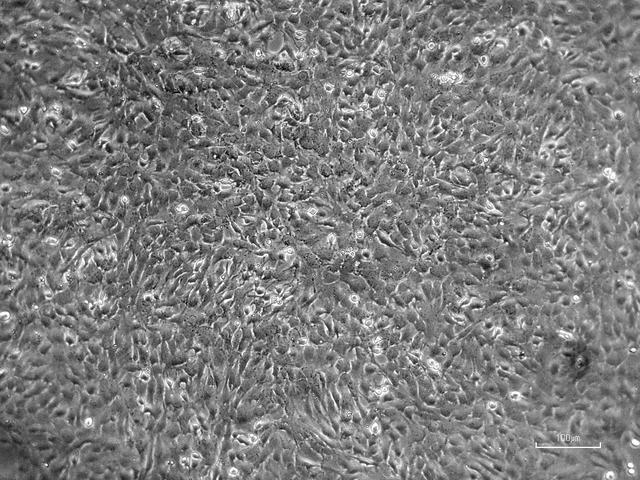

NASA image: OVOSPACE

Image

Apr 12, 2021

OVOSPACE

jsc2022e072967 (4/12/2021) --- Image of bovine ovary Granulosa cells. Coordinated by the Italian Space Agency (ASI),...

JSC